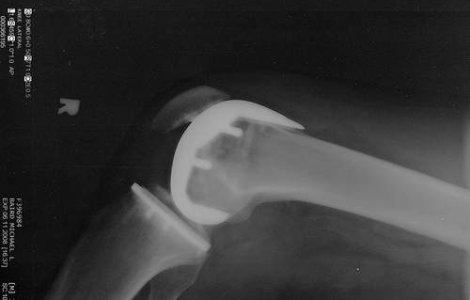

Pacientii romani diagnosticati cu artroza pot beneficia, si la Hyperclinica MedLife Grivita din Bucuresti, de o terapie inovatoare contra acestei afectiuni, datorita careia se pot bucura de doi ani de confort si de sansa de a amana protezarea, potrivit specialistilor in ortopedie.